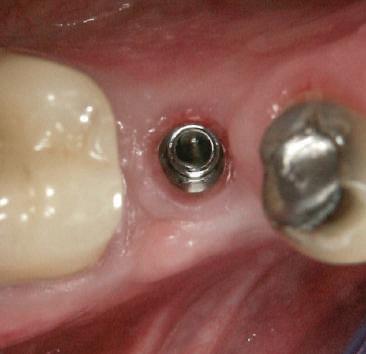

Cazul (4)

Bonturi provizorii

Acest pacient s-a prezentat cu dentiţia mandibulară laterală dreaptă eşuată din cauza unei fracturi radiculare verticale şi a cariei secundare. Autorii au utilizat cilindri de bonturi provizorii, cu şurub, ca metodă iniţială de retenţie pentru puntea provizorie după prima etapă de tratament, care a inclus extracţii şi inserarea de implanturi. Atitudine: Cilindrii temporari înşurubaţi pe implanturi după inserare sunt prezentaţi în fig 13. Ei au fost cimentaţi la carcasa acrilică prefabricată construită pe baza wax-up-ului diagnostic al pacientului (fig. 14). După îndepărtarea acrilatului excesiv, s-a

inserat proteza provizorie fixată cu şurub (fig. 15).

Cazul (4): Bonturi provizorii

Figurile

13. Cilindrii temporari înşurubaţi pe implanturi.

14. Cilindrii cimentaţi la o carcasă prefabricată din acrilat.

15. Proteza fixă provizorie fixată cu şuruburi.